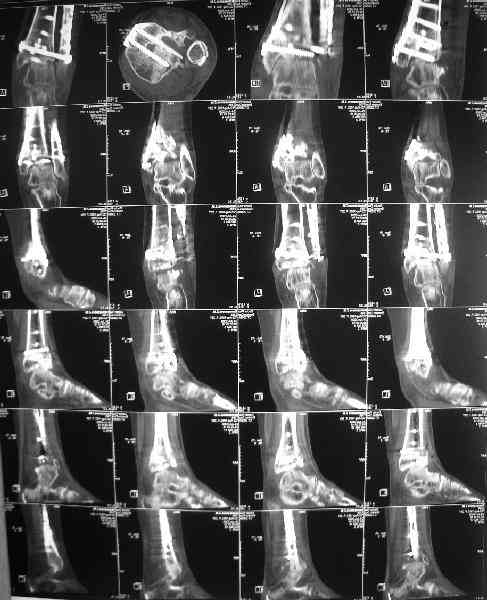

She has an intraarticular screw on CT, best is to remove all and wait untill she asks for fusion.

CT images/xrays confirm incongruity of articular surfaces as well as intraarticular screws.

removing just those screws which have penetrated the joint may take some pain away.

Eventually fusion will be indicated. (her age is 25 and she is not suitable for ankle replacement. Good prostheses like 'STAR' ankles are available but not suitable at this age. A failed ankle replacement will be a difficult situation to deal with in a young patient)